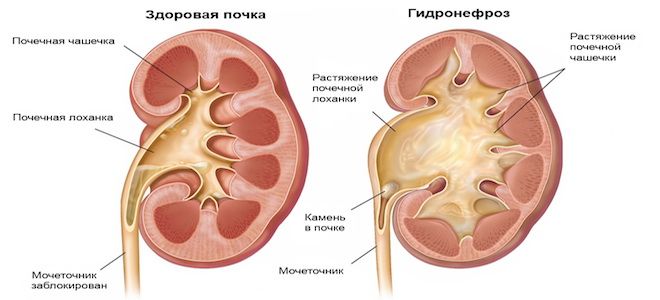

Интраренальная лоханка: рентгеновские снимки и примеры